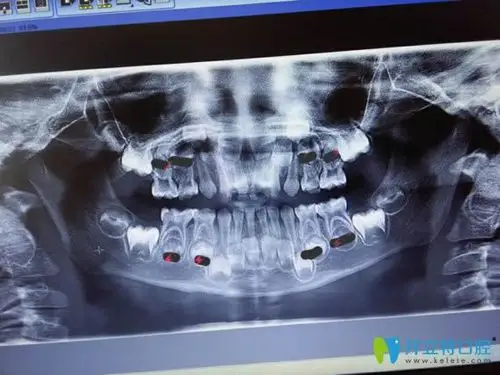

图片慎入!你们知道有个东西叫"儿童牙片"吗?

儿童牙科x光全景图

5岁小孩的牙片!

全景牙科 x 射线八岁儿童的问题不松动他的乳牙-持续乳牙

9周岁的孩子牙齿反合去拍了个牙片,结果医生说左门牙牙根处还有问题

儿童牙片显示图